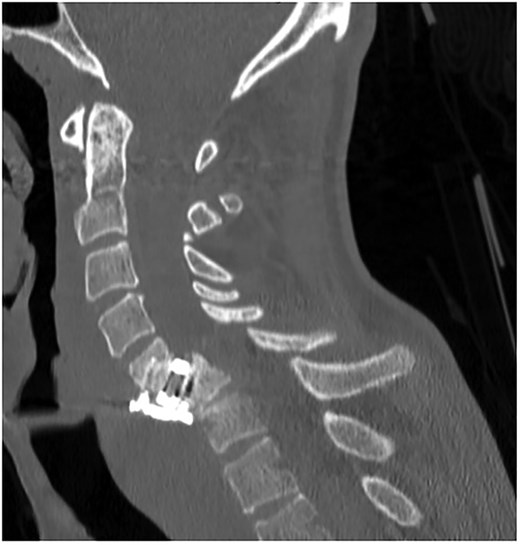

A 35-year-old male presented with a month-long history of dysphagia, severe headache, and posterior neck pain that radiated to the occiput. His medical history was significant for cervical surgeries, including an anterior cervical discectomy and fusion (ACDF) at C5/C6 one year and two months ago (Fig. 1). Shortly thereafter, the patient underwent revision surgery along with posterior plating from C5 to T1 due to osteomyelitis, worsening cervical deformity, and retropharyngeal abscess (Fig. 2). Initial workup included a noncontract computed tomography (CT), demonstrating increased gas density at C6 corpectomy site and post cricoid region (Fig. 3). A swallow study was obtained based on suspicion of a perforation and demonstrated extraluminal leakage of contrast posteriorly at the C6 level, consistent with initial CT (Fig. 4). Surgery included removal of the anterior and posterior hardware and esophageal repair. Although initially the esophageal injury was suspected to be related to the hardware, intraoperatively, it was found the instrumentation was not in communication with the esophagus. This confirmed the perforation was unrelated to direct injury from the cervical hardware construct, which was intact. The esophagus was repaired with a pectoralis flap. The postoperative course was uneventful, and the patient was discharged home after one week. The patient later died due to severe complications of substance abuse unrelated to the operation.

Swallow study demonstrating extraluminal leakage of contrast posteriorly at the C6 level consistent with CT findings.